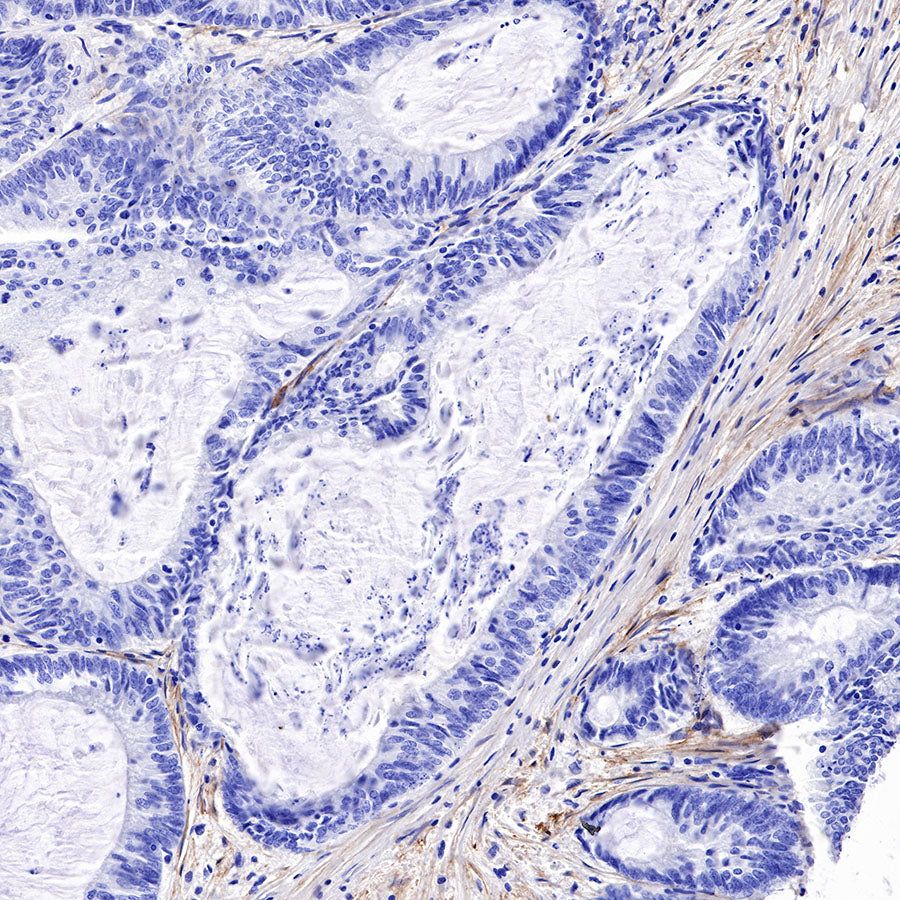

Immunohistochemistry

IHC shows positive staining in paraffin-embedded human cervical squamous cell carcinoma. Anti-FAP antibody was used at 1/500 dilution, followed by a HRP Polymer for Mouse & Rabbit IgG (ready to use). Counterstained with hematoxylin. Heat mediated antigen retrieval with Tris/EDTA buffer pH9.0 was performed before commencing with IHC staining protocol.